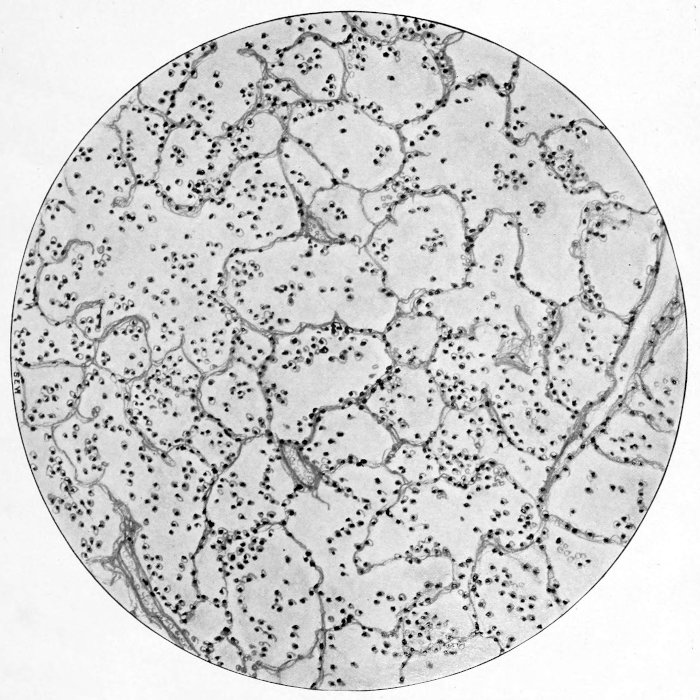

subscribe to our email newsletter to hear about new eBooks.